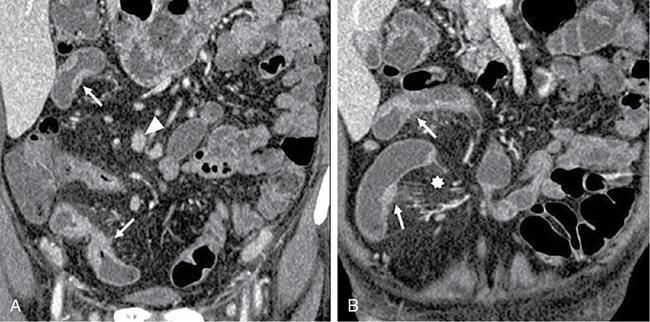

Kavita Saggar, Archana Ahluwalia, Devinder Pal Singh Dhanota, Geetika Khanna, Chander Gupta Inflammatory bowel disease (IBD) represents chronic idiopathic inflammation of the gastrointestinal [GI] tract. The common subtypes are Crohn’s disease, ulcerative colitis (UC) and indeterminate colitis (Fig. 7.11.1). Approximately 20%–25% of patients present in childhood or adolescence. Of these, nearly two-thirds of cases are caused by Crohn’s disease with an incidence of 4.56 per 1000,000 children (Fig. 7.11.2). IBD can affect any portion of the GI tract; however, children have a much higher incidence of small bowel and colonic involvement (Table 7.11.1). Currently, there is no single diagnostic test for the evaluation of IBD. Diagnosis is based on a combination of history, physical examination, serum inflammatory markers, endoscopy, histopathology and imaging. A host of imaging modalities is available for the evaluation of IBD in children. Traditionally, barium fluoroscopic studies, namely small bowel follow-through or small bowel enteroclysis (SBE) were used. However, barium studies depict only the mucosal abnormalities and do not evaluate the extraluminal extent of disease. Ultrasonography (US) is increasingly being used in the workup of patients with IBD. Small intestine contrast ultrasound (SICUS) and contrast-enhanced ultrasound (CEUS) are used for evaluation of IBD. CEUS requires intravenous administration of microbubble contrast such as Sonovue, and SICUS requires small bowel adequate luminal distension with ingestion of an iso-osmolar contrast agent such as polyethylene glycol. A recent meta-analysis of 33 studies showed that CEUS had better accuracy than US, CT and MR for the detection of inflammation and differentiation of fibrotic and inflammatory strictures. However, the extent of the disease was better evaluated by CT and MR. Currently, computed tomography enterography (CTE) and magnetic resonance enterography (MRE) have emerged as the most effective tools for imaging small bowel in patients with IBD. CTE and MRE can accurately depict the spectrum of imaging findings related to severity, extent and complications of IBD and thereby help in guiding management and assess the response to treatment. MRE is an attractive imaging modality due to lack of ionizing radiation, inherent multiplanar capability and excellent soft tissue contrast resolution. In addition, dynamic/cine imaging allows assessment of peristalsis and accurate identification of the diseased segment. The major disadvantage of MRE is high cost, lower spatial and temporal resolution and long examination time. Crohn’s disease is a transmural granulomatous disease that can affect any part of the GI tract from the oral cavity to anus, often involving multiple discontinuous segments of bowel. Patients have a genetic predilection to develop an abnormal immunologic response to environmental factors including food and gut flora, leading to a chronic inflammatory response. Small bowel is the major site of involvement. Terminal ileum is the most common location which is involved in approximately one-third patients. The colon is affected in 50% patients. In 15%–20% cases, there may be isolated involvement of the colon without affecting the small bowel. The clinical importance of small bowel Crohn’s disease is the impact that a diffuse small bowel disease is expected to have on child’s growth and development. Thus, objective evaluation of small bowel is essential in differentiating from other enteropathies and in directing the management of patients with IBD. Two methods used for imaging small bowel with barium using fluoroscopy are standard small bowel follow through (SBFT) and SBE. Small bowel evaluation with barium has long been considered the most common, noninvasive, inexpensive and easily accessible radiological method, but it has been replaced by cross-sectional imaging. In the current scenario, the only indication of barium studies is when CTE or MRE cannot be done because of nonavailability or are not feasible. Ultrasound is being increasingly used to assess the activity of Crohn’s disease, especially in paediatric patients. Greyscale ultrasound allows morphologic assessment of bowel wall and mesentery. Normal small bowel loops are easily compressible with the transducer and the wall thickness is <2 mm. The bowel loops show regular peristalsis and are mobile. Colour Doppler shows minimal intramural or perienteric vascularity. The salient sonographic features of Crohn’s disease are: There is marked concentric or eccentric bowel wall thickening [>2.5–3 mm]. The mural echogenicity depends upon the degree of inflammation and fibrosis. In the acute phase, mural stratification is maintained (Fig. 7.11.3A and B). In patients with long-standing disease, a target or pseudo-kidney appearance may be seen. In long-standing burnt-out disease, there is submucosal fat deposition. The actively inflamed bowel segments show increased vascularity on Doppler ultrasound (Fig. 7.11.4A and B). CEUS with microbubbles can objectively assess the disease activity. A stricture is seen as a segment of bowel wall thickening with apposition of the luminal surfaces. There is persistent luminal narrowing with variable degree of upstream dilatation and hyperperistalsis. Doppler imaging reveals hyperemia in strictures with an active inflammatory component. Fibrotic strictures do not demonstrate increased blood flow. A major advantage of ultrasound is real-time imaging which allows the evaluation of bowel peristalsis. The diseased segments of the bowel (inflamed or fibrotic) show reduced peristalsis and often appear fixed in position. Mesenteric inflammation is commonly seen in active Crohn’s disease. Sonography reveals thickening of mesentery with heterogeneous echogenicity due to oedema. Doppler ultrasound shows increased vascularity due to engorgement of vasa recta. Fibrofatty proliferation of mesentery seen in chronic disease appears as abnormally thickened echogenic fat that displaces the bowel loops. Reactive mesenteric lymph nodes (up to 1.5 cm) can be seen in the active inflammatory phase of Crohn’s disease. These appear as hypoechoic round or oval structures with preserved fatty hilum. Sinus tracts and fistula often arise from or just proximal to a strictured segment and appear as linear areas of altered hypoechogenicity extending from serosal surface of gut. There may be tethering and/or angulation of the affected bowel segment. Abscesses are discrete well-defined fluid collections with internal debris, septation or nondependent echogenic gas. Colour Doppler reveals peripheral hyperemia with absent blood flow centrally. Ultrasound may be falsely negative if an abscess contains a large amount of air and can be mistaken for an air-filled bowel loop. Both CTE and MRE identify the transmural, extramural and mesenteric manifestations of small bowel Crohn’s disease. The imaging findings can be categorized as: Asymmetric long segment (>3 cm) bowel wall thickening is a consistent feature of Crohn’s disease. The mesenteric border is usually more severely affected. It is imperative that the bowel should be distended when assessing bowel wall thickening. Thickening may be mild (3–4 mm), moderate (5–10 mm) or severe (>10 mm) (Fig. 7.11.5A and B). This is the most consistent finding in the active inflammatory stage, defined as increased signal intensity or attenuation on contrast-enhanced scans in a noncontracted segment of bowel in comparison with adjacent small bowel segments. Hyperenhancement may be stratified into bilaminar and trilaminar patterns. In the bilaminar pattern, there is hyperenhancement of only the inner wall (often referred to as mucosal hyperenhancement), and in the trilaminar pattern, there is inner and outer wall hyperenhancement, with the submucosal oedema giving a halo effect. Hyperenhancement may also be homogeneously transmural or patchy. A potential pitfall in contrast enhancement is that normal jejunal loops enhance more than ileal loops and collapsed bowel segments can show apparent hyperenhancement (Figs. 7.11.6A,B and 7.11.7A–C). These are defined as multifocal (>3) segmental areas of involvement with normal intervening gut loops. This is an important feature that differentiates Crohn’s disease from UC when colon is predominantly involved (Figs. 7.11.5A,B and 7.11.7A–C). This is identified as an increased signal of the thickened bowel wall on T2W images. The inflamed walls also show restricted diffusion. The hyperintense signal due to intramural oedema persists on T2W fat-saturated images differentiating it from intramural fat seen in long-standing burnt-out disease (Fig. 7.11.8A and B; refer Fig. 7.11.20A–D).